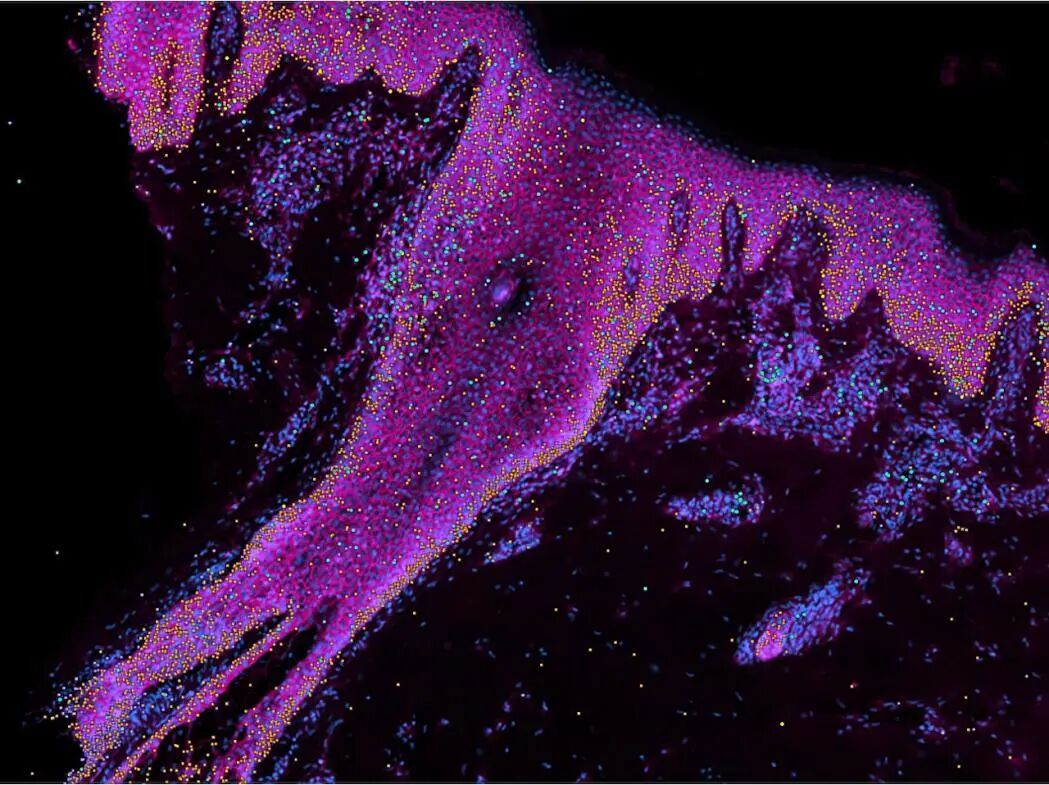

图片

△ 分割染色后的人类皮肤细胞。(粉色:细胞膜。蓝色:细胞核。黄色绿色:内部细胞染色。)来源:威康桑格研究所